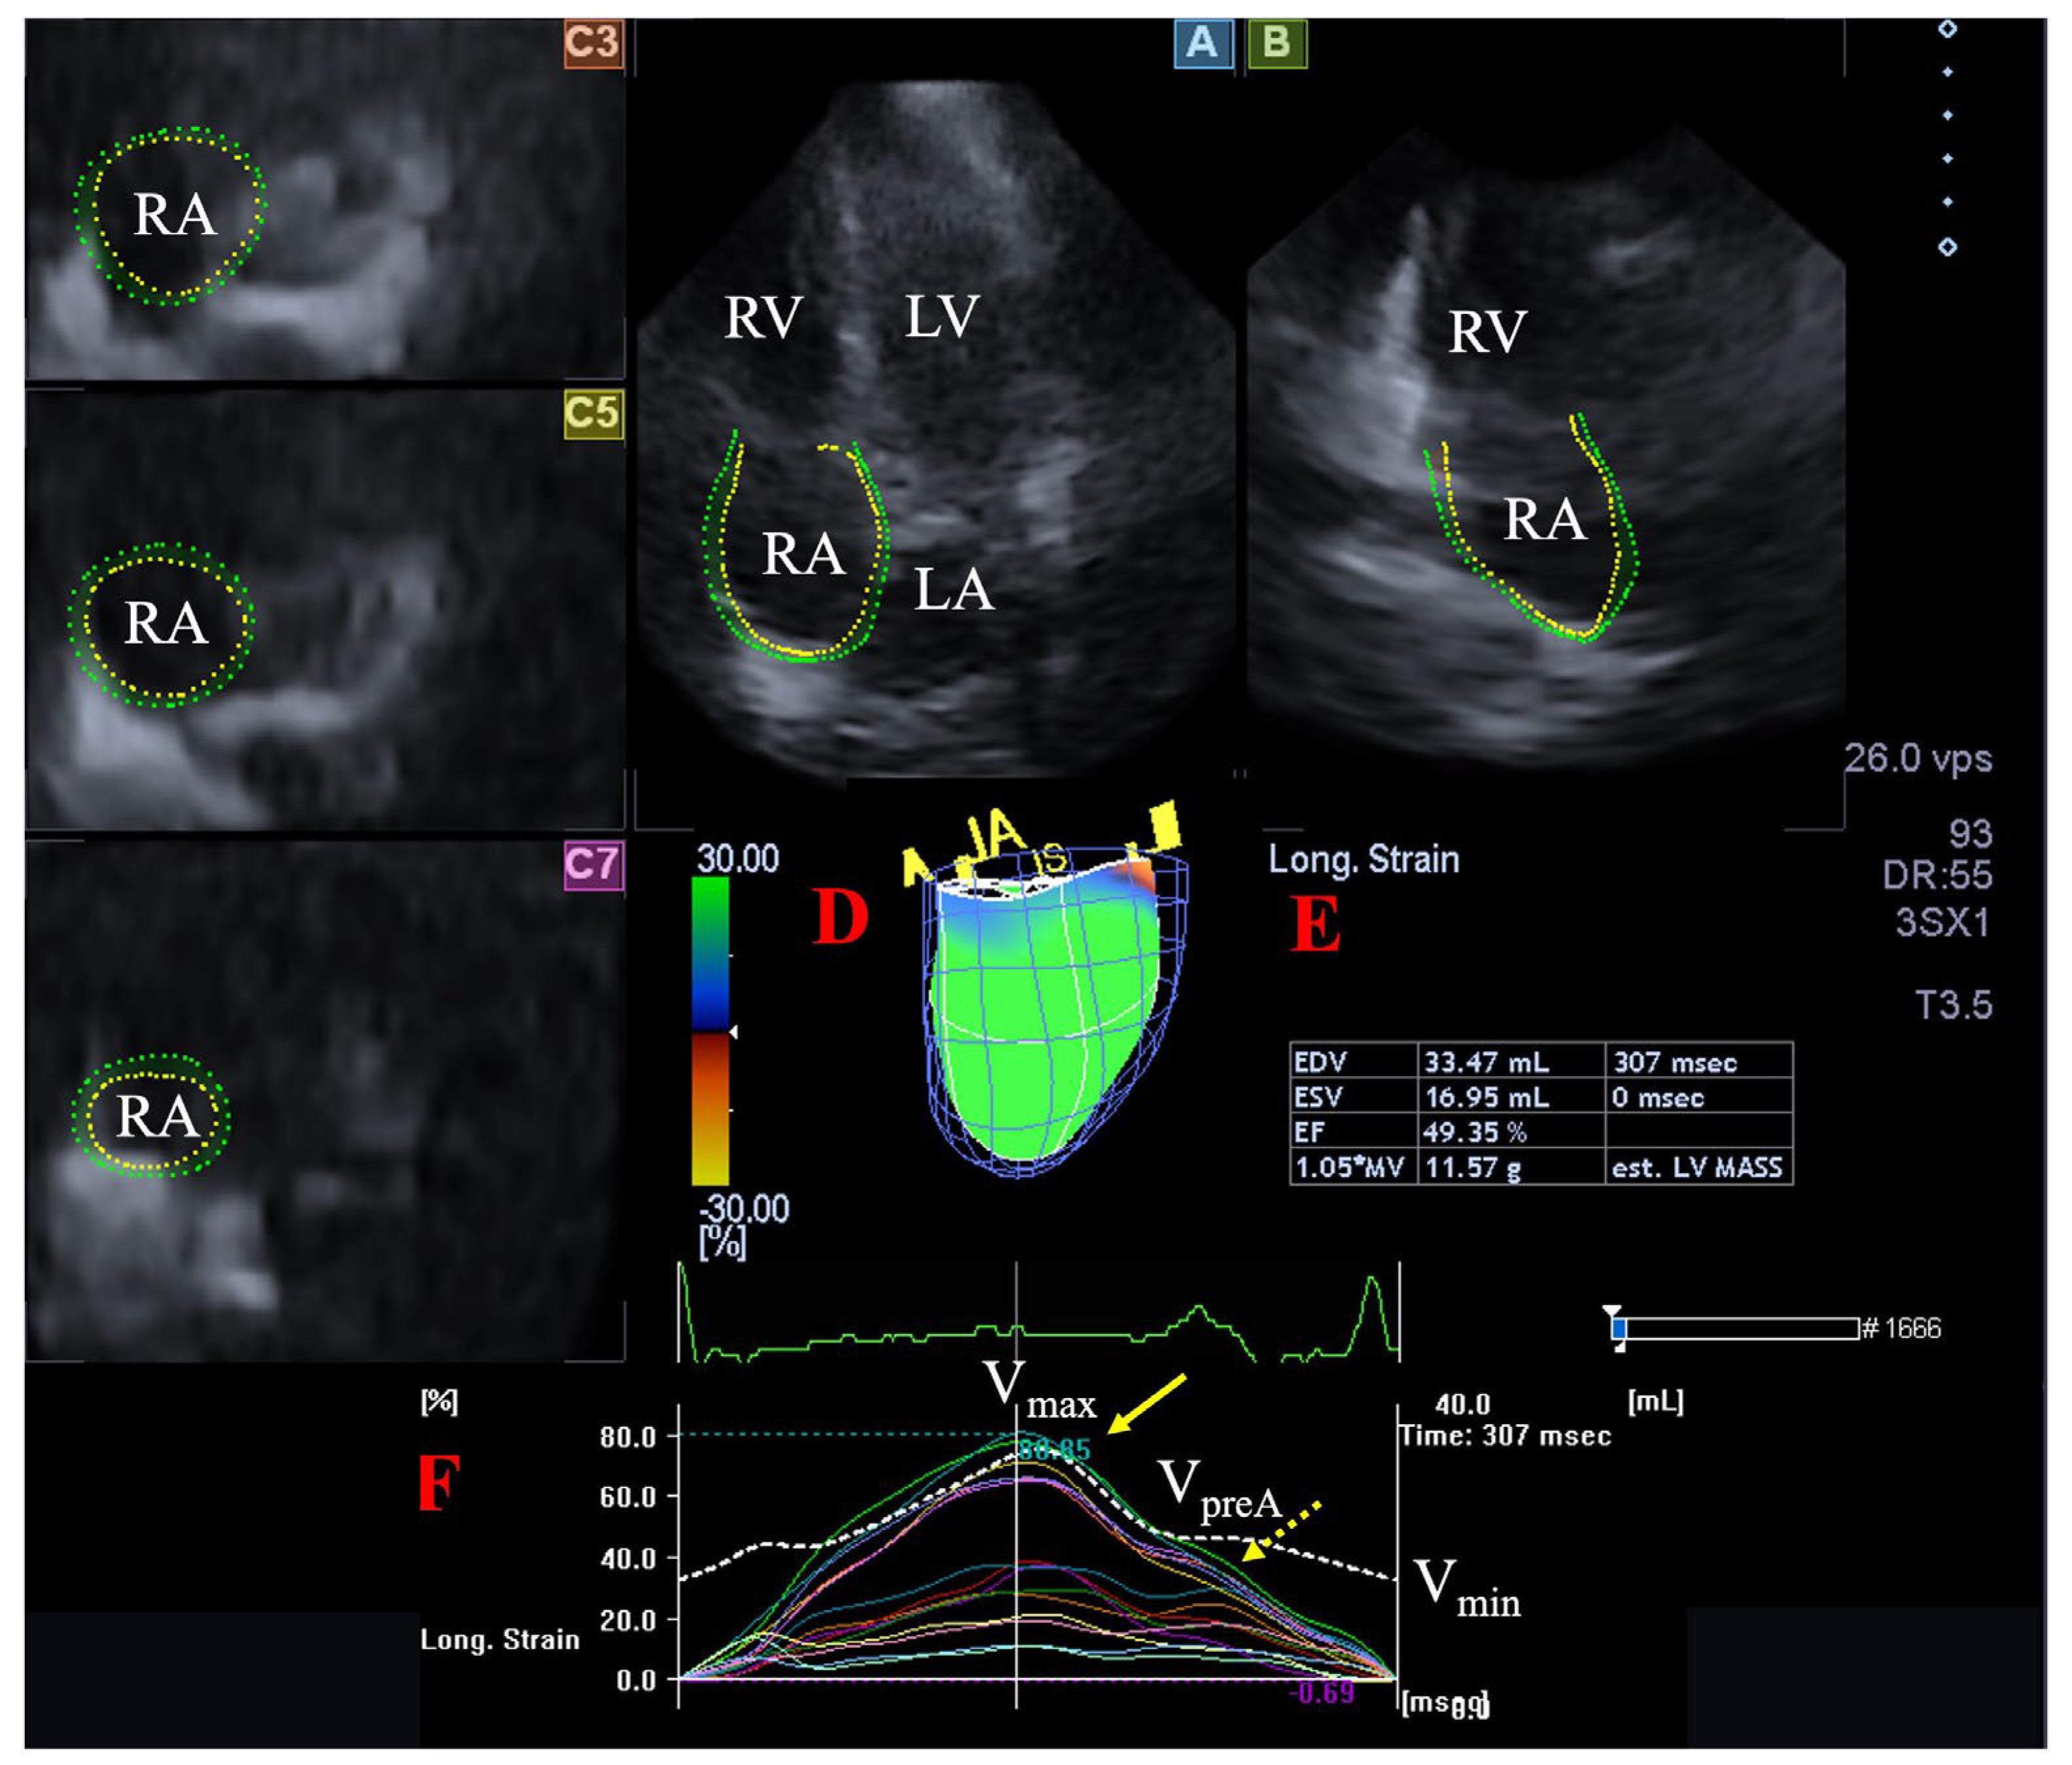

During offline analysis, the vendor-provided 3D Wall Motion Tracking software version 2.7 (Ultra Extend, Toshiba Medical Systems, Tokyo, Japan) was used. Automatically selected apical two-chamber (AP2CH) and four-chamber (AP4CH) views and 3 short-axis views at basal, midatrial and superior levels acquired at end-diastole were used for the presentation of the acquired 3D data, and data were displayed on 2D images. Then, a 3D RA model was created by using reference points on the RA endocardium in AP2CH and AP4CH views on the edges of the TA ring and the RA apex at end-diastole. Following these definitions, automatic sequential analysis (reconstruction) was started. Using the created 3D cast, the following RA volumes were calculated (Figure 1) [9,19]:

Figure 1.

Assessment of the right atrium (RA) is presented extracted from a three-dimensional (3D) echocardiographic full-volume dataset: apical four-chamber view (A), apical two-chamber view (B), short-axis views at basal (C3), midatrial (C5), and superior (C7) RA levels. Virtual 3D cast of the RA (D), calculated RA volumes (E) and RA volume changes (dashed white line), and global and segmental RA (longitudinal) strain changes (white and coloured lines) over time (F) are also presented. Yellow arrow represents peak RA strains (dashed yellow arrow represents RA strains at atrial contraction, not examined). Abbreviations. LA = left atrium, LV = left ventricle, RA = right atrium, RV = right ventricle, Vmax = end-systolic maximum RA volume, Vmin = end-diastolic minimum RA volume, VpreA = preatrial contraction RA volume.

- Maximum RA volume, measured at end-systole, just before tricuspid valve opening (Vmax).

- RA volume before atrial contraction, measured at early-diastole at the time of P wave on ECG (VpreA).

- Minimum RA volume measured at end-diastole, just before tricuspid valve closure (Vmin).

The following RA strains were determined regarding the RA reservoir function in end-systole (peak strains) [9,20]:

- Radial strain (RS) representing the thickening/thinning of a certain RA segment.

- Longitudinal strain (LS) representing the lengthening/shortening of a certain RA segment.

- Circumferential strain (CS) representing the widening/narrowing of a certain RA segment.

Global (assessing the whole RA), mean segmental (average of 16 segmental strains) and basal regional (average of 6 basal strains) peak RA strains were calculated.